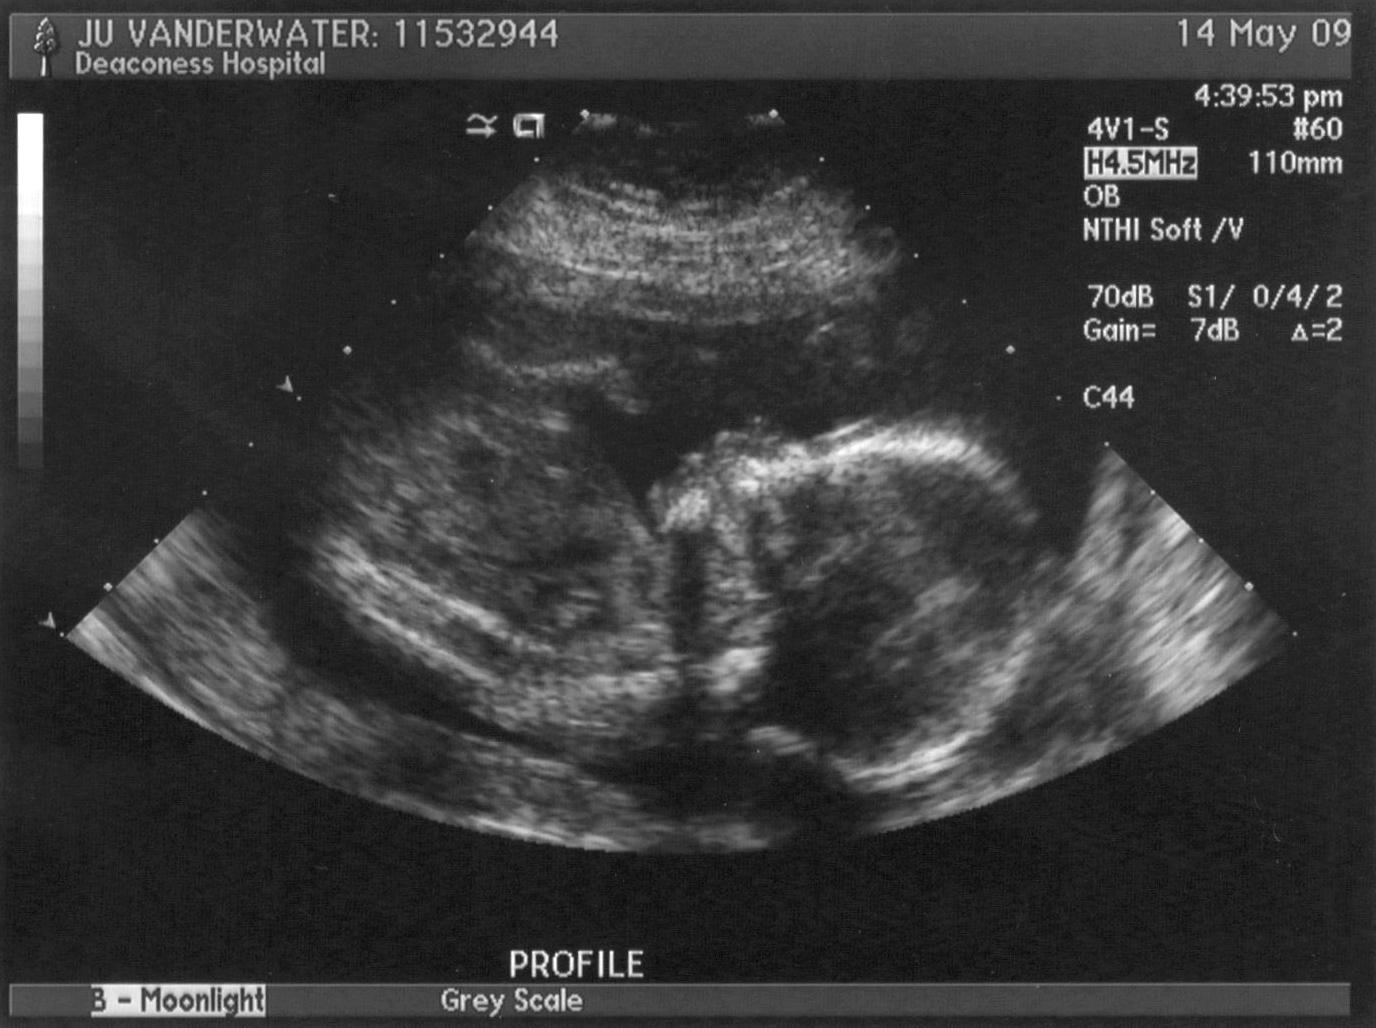

Our baby V's gorgeous profile pics. :D (They're the same, just different color. Check out the nose and the lips!! Hope the baby has Daddy's perfect nose...) Image Image Add new comment Your name Email The content of this field is kept private and will not be shown publicly. Homepage Subject Comment About text formats Leave this field blank